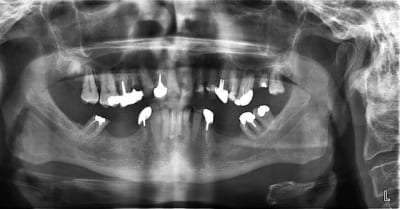

bon, difficile d'évaluer à distance...au vue de la pano et de tes photos...voilà ce que je ferais...:

-extrac de 14 et 27

-après les dévit qui s'imposent (même avec la pulpe dans les chaussettes)bridge sup en 2 parties, de 11 à 16 (que tu peux garder vivante) et 21 à 26

-Bridges inf en 3 parties, 33 à 37, 32 à 42, 43 à 47

J'ai fait une RA de 22, elle est très courte et cariée assez sous gingivale. Pas sûr du tout de la conserver.

Suis pas très chaud pour garder la 12 (LPA sous richmond)

Il y a une péche sous 26. Faut qu'on soit sûr de la garder avant de se lancer dans un bridge.

J'ai pensé aussi comme toi au bridge 32-42 mais la forme de la racine de 32 n'est pas idéale.

Après il faut raisonner par sextant et ne pas hésiter à faire le ménage dans les secteurs trop compromis: 14 à 18 me paraissent bonne pour le cimetière des dents, de l'autre côté c'est à confirmer par des rétros mais ça n'a pas l'air beaucoup plus glorieux; en bas les secteurs postérieurs ne sont pas terribles non plus si tu considères que la première molaire secteur 3 n'est pas conservable, tu peux abandonner la deuxième aussi; secteur 4 ta molaire pourrait te servir d'appui pour une éventuelle PAP.

Pour la DV, une fois que toutes les dents égressées ont été retirées, je ne pense pas que tu auras de problème de place particulier, à confirmer avec les modèles (il faut juste compenser la perte de substance des molaires mandibulaires).